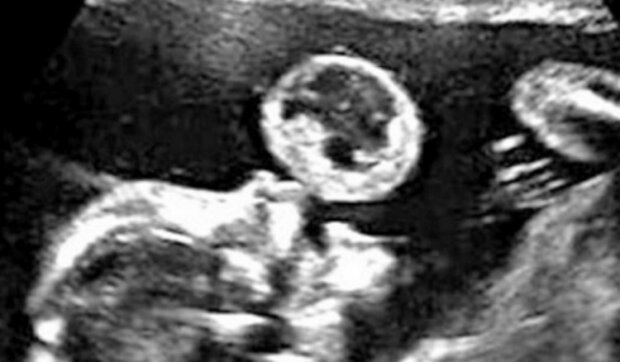

Tammy Gonazalez z Miami na Floridě byla na rutinním ultrazvuku. Najednou si všimla, že její dítě z úst vyfukuje obrovskou bublinu.

Po důkladném vyšetření plodu lékaři řekli něco hrozného. „Bublina“ se ukázal jako teratom, což je velmi vzácná rakovina.

Dítě nevyfouklo z úst bublinu. Místo toho se tam vyvinula rakovina.